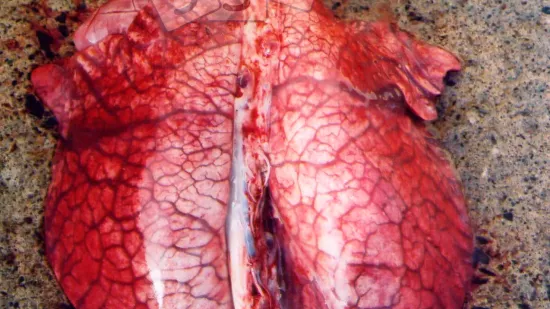

Il y a une épidémie de morts subites, perte d'appétit, forte fièvre et respiration laborieuse chez des porcs de 15 semaines jusqu'à l'abattage. L'inspection à l'abattoir montre des poumons comme ceux de la photo. Quelle est la cause la plus probable?